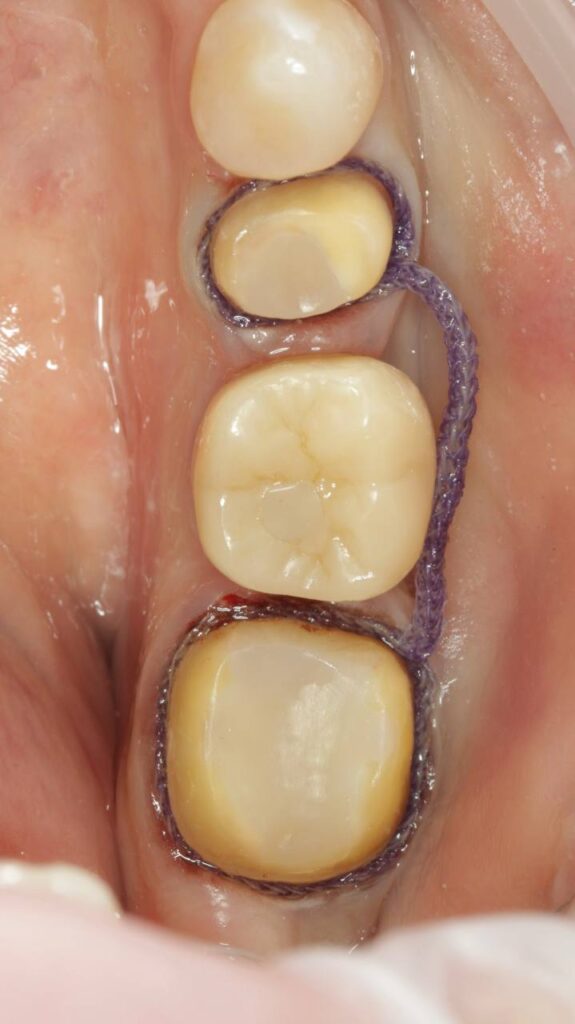

Протезирование коронками из диоксида циркония, после эндодонтического лечения — Исламов Л.А.(01.04.2026)